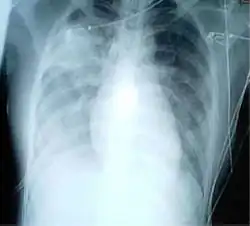

Gallery

-

Chest X-ray PA inverted and enhanced. -

Projectionally rendered CT scan, showing the transition of thoracic structures between the anteroposterior and lateral view -

Chest film showing increased opacity in both lungs, indicative of pneumonia -

A chest radiograph showing bronchopulmonary dysplasia. -

A chest film after insertion of an implantable cardioverter-defibrillator, showing the shock generator in the upper left chest and the electrical lead inside the right heart. Note both radio-opaque coils along the device lead. -

Portable chest (ie, antero-posterior view) showing endotracheal tube and Levin tube, both properly in place.